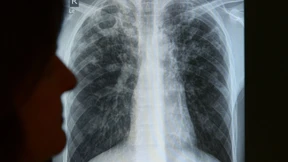

Tuberkulose tödlicher als HIV und Malaria

An Tuberkulose sterben inzwischen mehr Menschen als an HIV und Malaria zusammen. Vor allem die multiresistente Form der Tuberkulose, gegen die es kaum Medikamente gibt, bereitet der WHO Sorgen.